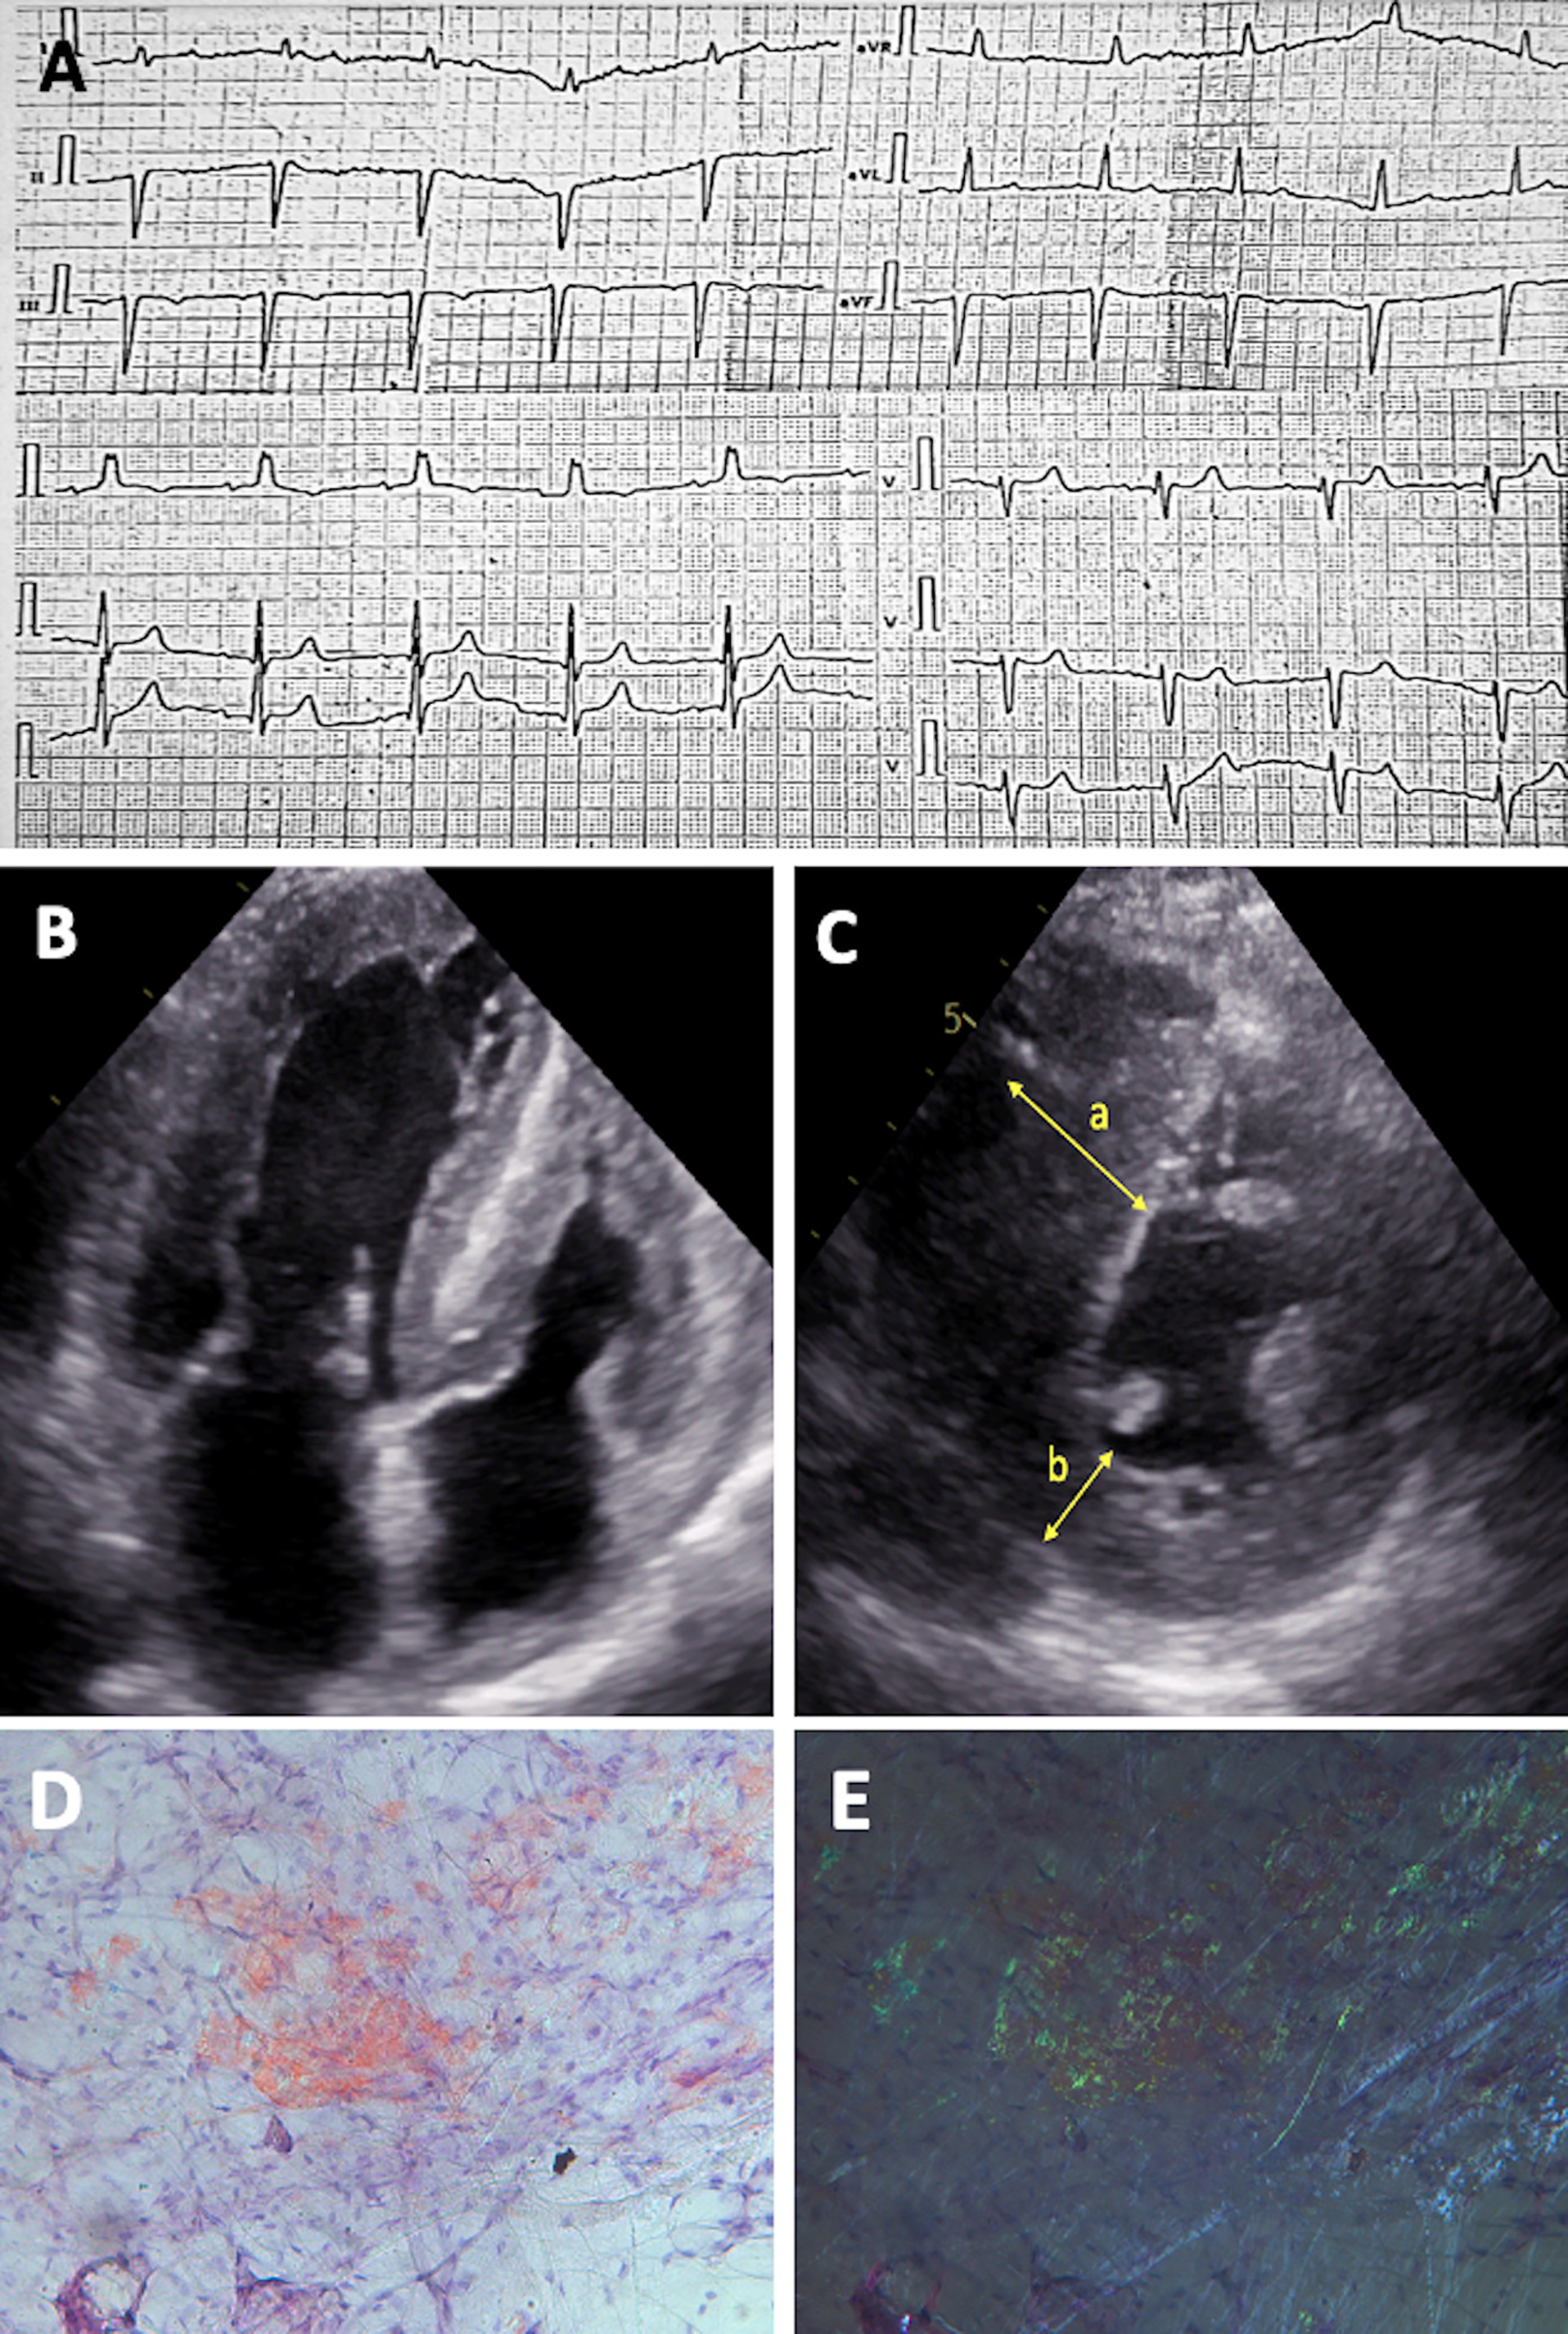

Figure 1

Diagnostic features of patient with hereditary ATTR amyloidosis. (A) ECG showing “normal” QRS voltage with left anterior hemiblock and right ventricular hypertrophy. (B) 2D ECHO in the apical four-chamber view and (C) short-axis view, revealing biventricular concentric hypertrophy with LV hypertrabeculation; measurements include interventricular septum thickness of 25 mm (a) and posterior wall thickness of 9 mm (b) (D–E) Histological slides of crushed subcutaneous fat tissue, stained with Congo red, at original magnification 200×. Under normal light, congophilic deposits are visible, and under polarized light, the typical birefringence of congophilic deposits is observed, graded as CR 3+ (according to B.P. Hazenberg).